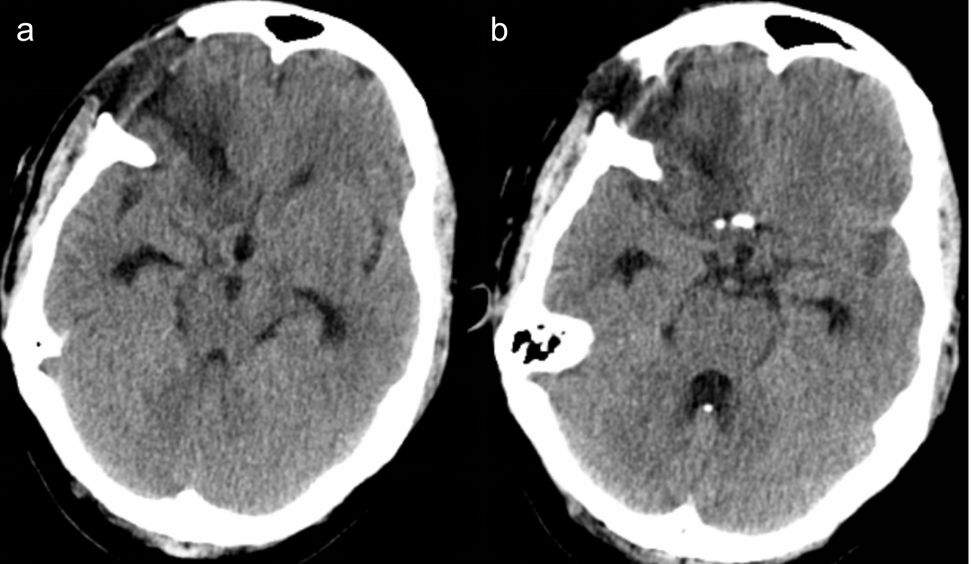

根据DSA检查结果及动脉瘤位置形状等,与家属沟通,急诊行右侧眶外侧入路前交通动脉瘤夹闭术+腰大池置管引流术。术后第1天患者神清,GCS14分,双侧瞳孔等大等圆,直径约为3mm,对光反射灵敏。术后第1天腰大池脑脊液引流量170ml。复查头颅CT示术区少量积血伴水肿,环池较术前明显变小(图2a,b)。

术后第2天晚患者意识逐渐变差,呈浅昏迷,GCS9分,右侧瞳孔直径约为3.5mm,左侧瞳孔直径约为3mm,对光反射差。术后第2天腰大池脑脊液引流量300ml。急诊查头颅CT示术区一小血肿,水肿明显,中线移位,环池消失(图2c,d)。

图2. 术后复查头颅CT: a-b)术后第1天示术区少量积血伴水肿,环池较术前消失;c-d)术后第2天示术区积血水肿,中线移位,环池消失。